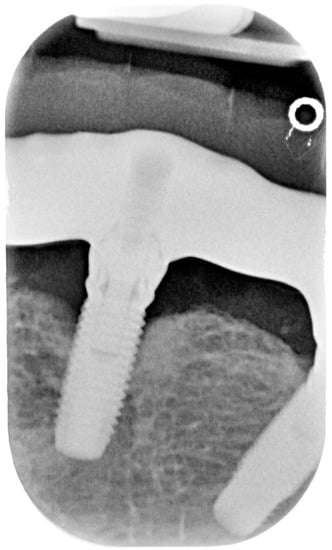

Figure 2.

X-ray of dental implant area before treatment.

Figure 5.

X-ray of dental implant area after treatment.